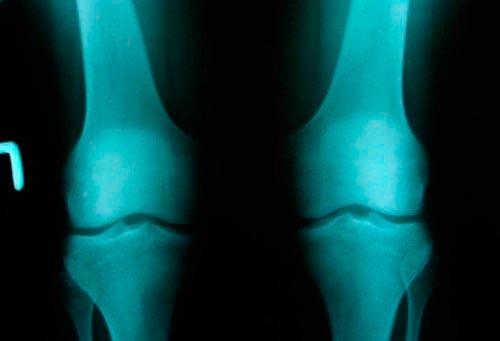

Рассматривая вопрос о признании страдающего гонартрозом человека инвалидом, медицинская комиссия принимает во внимание не выраженность болевого синдрома, а степень ограничения подвижности ноги в суставе, нарушения СДФ. Явления костной деформации и разрушения хряща должны быть подтверждены рентгеновскими снимками и результатами артроскопии. Также учитывается продолжительность больничных, которые оформляли в связи с временной утратой трудоспособности.

При второй степени, к существующим симптомам добавляется хруст и прострел в коленях. Амплитуда движений сильно сужается. Боль проявляется периодически, часто — острыми приступами. При диагностике обнаруживают сужение щели сустава, истончение диска и разрастание костной ткани.Третья степень характеризуется полным или частичным обездвиживанием суставов. Гиалиновый хрящ разрушен, а на рентгене присутствует разрастание костной ткани с образованием остеофитов (шпор). Нарушается циркуляция крови, теряется чувствительность пораженного участка.

1 степень проявляется в виде незначительного нарушения подвижности сустава. Рентген показывает небольшое разрастание кости по краям впадины самого сустава, его щель сужена, имеются районы оссификации хрящевой ткани.

При артрозе коленного сустава 2 степени возникает грубый хруст при движении. Наблюдается общая невозможность передвигаться. При проведении рентгена видны большие области костных разрастаний, начинается субхондральный склероз, щель сустава сужается в два-три раза, по сравнению с показателями нормы.

Гонартроз коленного сустава 3 степени характеризуется утратой полноценного движения. Остаются только покачивания пораженным суставом. Он очень сильно деформируется. После рентгена можно увидеть отсутствие суставной щели. Сама поверхность расширена из-за разрастания ее краев. Деформирование остро выраженное, имеется уплотнение обоих эпифизов.